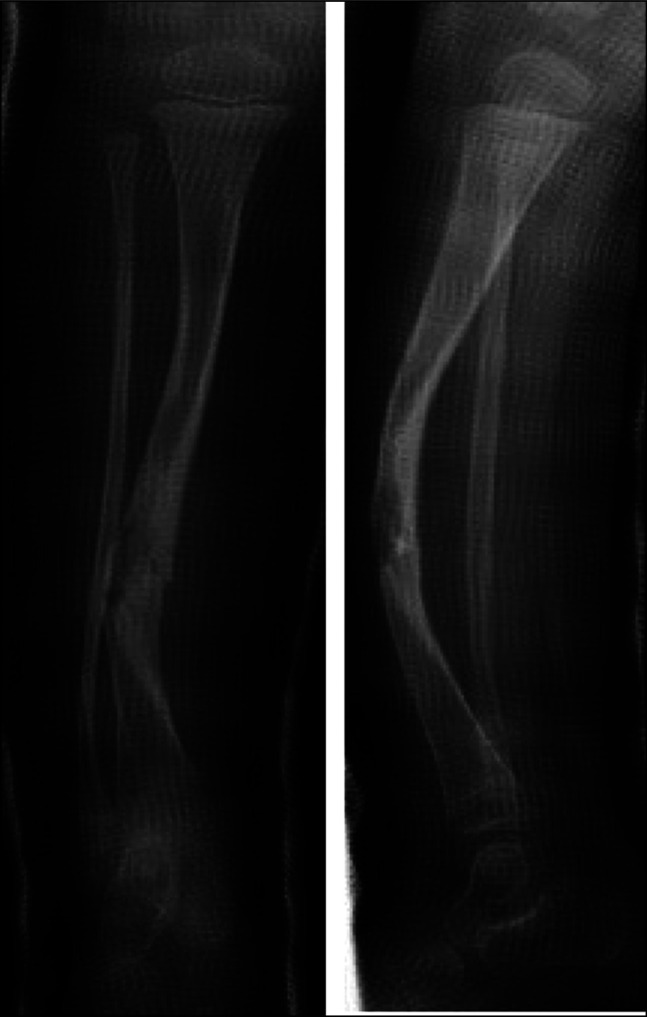

1型神经纤维瘤病(NF-1)导致皮肤、神经和肌肉骨骼表现。先天性胫骨假关节治疗被认为是实现骨愈合的积极手段。大多数患者在治疗结束时由于病理性骨切除和不对齐而导致肢体短。患者可能出现的表现之一是肢体局部半肥厚。在我们的病例中,我们首次报道了同一条腿先天性胫骨假关节和半肥厚并存的情况。

Neurofibromatosis type 1 (NF-1) leads to cutaneous, neurological, and musculoskeletal manifestations. Congenital pseudarthrosis of the tibia treatment is considered aggressive in achieving bone union. Most of those patients get a short limb at the end of treatment because of pathological bone resection and malalignment. One of the manifestations that can appear in patients is localized hemihypertrophy of the limb. In our case, we present the first time a coexistence of congenital pseudarthrosis of the tibia and hemihypertrophy in the same leg was reported.